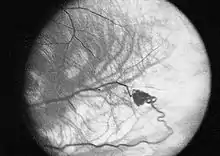

- Hemangioblastomas - tumores del sistema nervioso central (especialmente en el cerebelo, tronco del encéfalo y médula espinal). También se llaman así los que aparecen en la retina.

Eugen von Hippel fue quien primero describió los angiomas oculares (1904),[9] y Arvid Vilhelm Lindau describió los angiomas del cerebelo y la espina dorsal en 1927.[10]